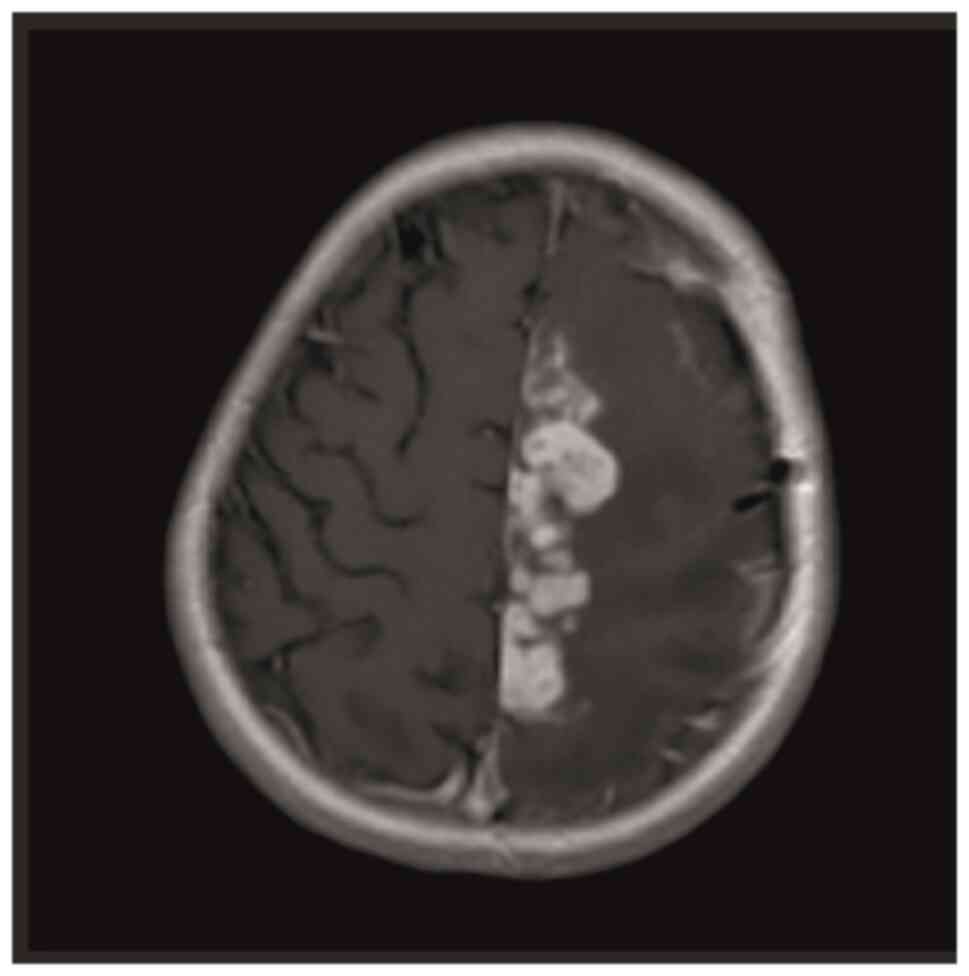

Intracranial tuberculoma represents one of the most severe complications of central nervous system tuberculosis (TB), with an incidence that is relatively low. In cases of intracranial tuberculoma, patients may develop drug toxicity and/or immune reconstitution inflammatory syndrome (IRIS) while receiving anti‑TB treatment. The current study presented the case of a seven‑year‑old female patient with intracranial tuberculoma who developed drug‑induced hepatotoxicity and IRIS during the course of treatment. During the follow‑up of the patient, anti‑TB drug‑induced hepatitis developed, which led to the discontinuation of the drug twice. In the seventh month of treatment, cranial MRI showed the progression of tuberculoma lesions. The possibility of IRIS or treatment failure was considered and the treatment was restarted with steroids and non‑hepatotoxic anti‑TB drugs. With steroid and anti‑TB treatment, the lesions regressed almost completely and the neurological deficit regressed. Patients receiving treatment should be followed up closely due to the possible side effects of anti‑TB drugs, especially IRIS, which develops as an immune restructuring response during the recovery of the immune system.

Figure 1

Figure 2

Figure 3

Figure 4

Figure 5